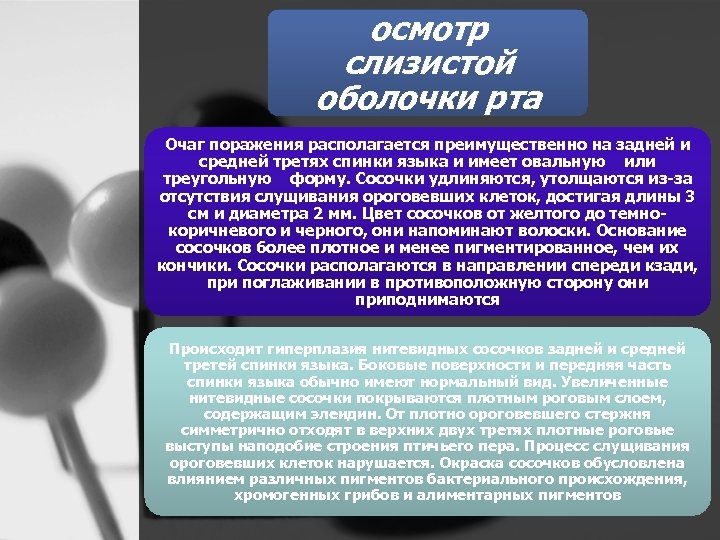

осмотр слизистой оболочки рта Очаг поражения располагается преимущественно на задней и средней третях спинки языка и имеет овальную или треугольную форму. Сосочки удлиняются, утолщаются из за отсутствия слущивания ороговевших клеток, достигая длины 3 см и диаметра 2 мм. Цвет сосочков от желтого до темно коричневого и черного, они напоминают волоски. Основание сосочков более плотное и менее пигментированное, чем их кончики. Сосочки располагаются в направлении спереди кзади, при поглаживании в противоположную сторону они приподнимаются Происходит гиперплазия нитевидных сосочков задней и средней третей спинки языка. Боковые поверхности и передняя часть спинки языка обычно имеют нормальный вид. Увеличенные нитевидные сосочки покрываются плотным роговым слоем, содержащим элеидин. От плотно ороговевшего стержня симметрично отходят в верхних двух третях плотные роговые выступы наподобие строения птичьего пера. Процесс слущивания ороговевших клеток нарушается. Окраска сосочков обусловлена влиянием различных пигментов бактериального происхождения, хромогенных грибов и алиментарных пигментов